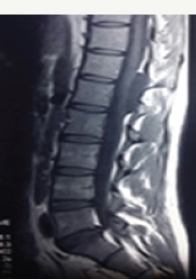

Figure 1a: Pre -operative T1 weighted sagittal MR imagesshowing hypointenseextradural lesion at dll- 12 level. Note the epidural fat capping at the superior and inferior margin of the lesion suggesting its extradural location.

Figure 1b: Pre-operative T2 weighted sagittal MR images showing CSF intensity lesion at d11-d12 level.

19 year male presented with a history of lower back pain of 6 months duration. It was insidious in onset, gradually progressive with mild weakness of both lower limbs. He had a past history of fall from a tree with sustained injury to back 10 years ago. On examination, he had paraparesis with power (grade 4/5). There were no bladder and bowel disturbances. Other physical findings were not remarkable. MRI dorsal spine with screening of the entire spine showed a small, elongated, well defined CSF signal intensity extradural cystic lesion at D11-12 level suggesting arachnoid cyst. The lesion was compressing the dorsal spinal cord from behind (Figure 1a-1c).

Magnetic resonance imaging appears to be effective as an initial modality for diagnosing arachnoid cysts and does not require the intrathecal injection of contrast medium. It can define the anatomical relationship to surrounding structures. The imaging characteristics of arachnoid cysts are similar to those of CSF signal intensity. Epidural fat capping of the lesion at its superior and inferior poles can be seen on sagittal T1-weighted MR images, which further suggests its extradural location. The presence of vertebral body scalloping and expansion of the neural foramina bilaterally from osseous remodelling suggests a longstanding mass effect from the lesion.